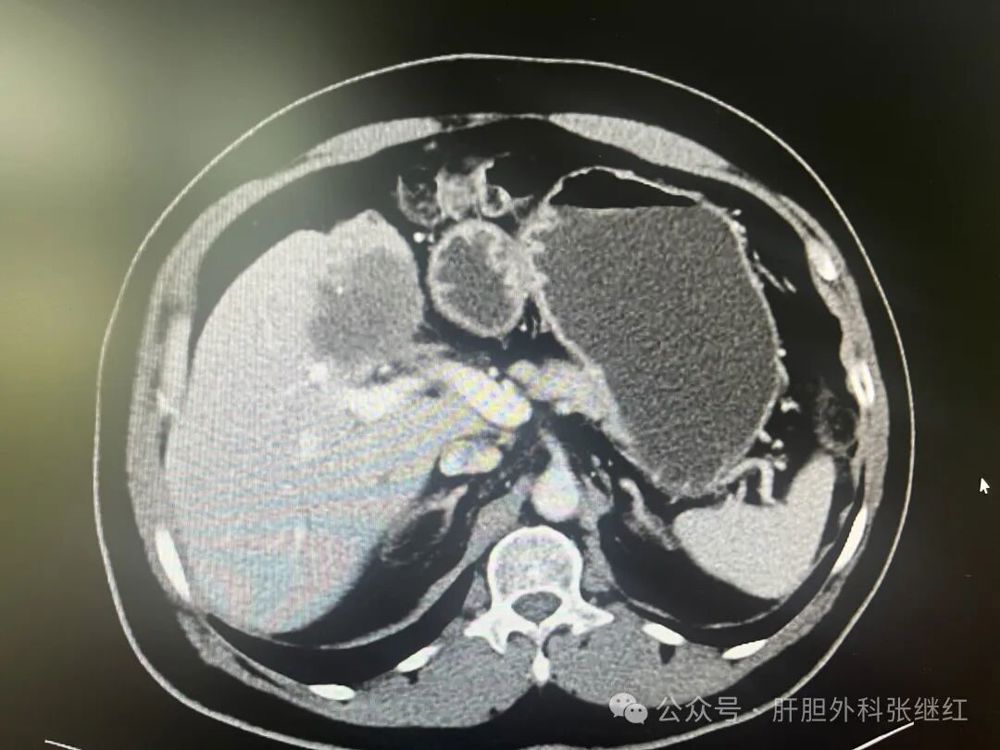

转化治疗后CT

该患者是佛山复星禅诚医院肝胆胰外科病例,张继红医生有幸参加了术前多学科会诊和手术。1年前,一男性56岁病人,经CT、MR等影像学检查和病理活检确诊为胆管细胞癌,瘤体巨大,长径超过10厘米,且伴门静脉左支癌栓形成和多发腹腔淋巴结转移,经多学科会诊后决定应用吉西他滨和奥沙利铂化疗联合PD-L1单抗(度伐利尤单抗)免疫治疗进行转化治疗后再手术切除。经上述化疗联合免疫治疗五个疗程(每次均为单次给药,间隔时间21天)治疗后肿瘤明显缩小,直径约5厘米,淋巴结病灶也有所减少或缩小,达到了影像学部分缓解和手术切除的标准,经多学科会诊后决定行扩大左半肝切除及区域淋巴结清扫术,术后再行辅助治疗。本为腹腔镜手术,术中见左肝肿瘤萎缩明显,肿瘤压迫右侧肝蒂,肝门部及肝总动脉周围未见明显肿大淋巴结,肝门部粘连严重,仅清扫12a、12b、7-9组淋巴结所在区域脂肪淋巴组织,解剖离断左肝动脉、门静脉左支及左肝管,发现肿瘤基本位于缺血范围内,超声引导下在缺血线和S5段肿瘤外侧画切肝线,拟切除包括胆囊的S5段和左半肝,15+5min模式间歇性阻断肝门,沿预切线离断肝实质,达右肝蒂时发现肿瘤紧贴右肝蒂,为避免右肝蒂损伤,中转开腹完成整块切除包括胆囊的S5段及左半肝。手术后病理证实肿瘤100%坏死,清扫淋巴结亦未发现肿瘤细胞,达到病理学完全缓解(pCR)。术后早期肝断面少许积液,经引流后积液消失。目前病人状态良好,已无瘤生存半年余。